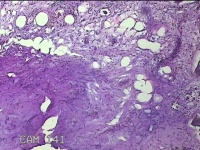

肛周外痔

性别

男

年龄

34岁

临床诊断

1.出血性内痔 2.混合痔 3.肛乳头肥大

一般病史

间断便血3年余。

标本名称

大体所见

灰白暗红色包块0.7x0.3x0.2cm一个,表面糜烂。

像痔。

有可能是外痔。猜的。